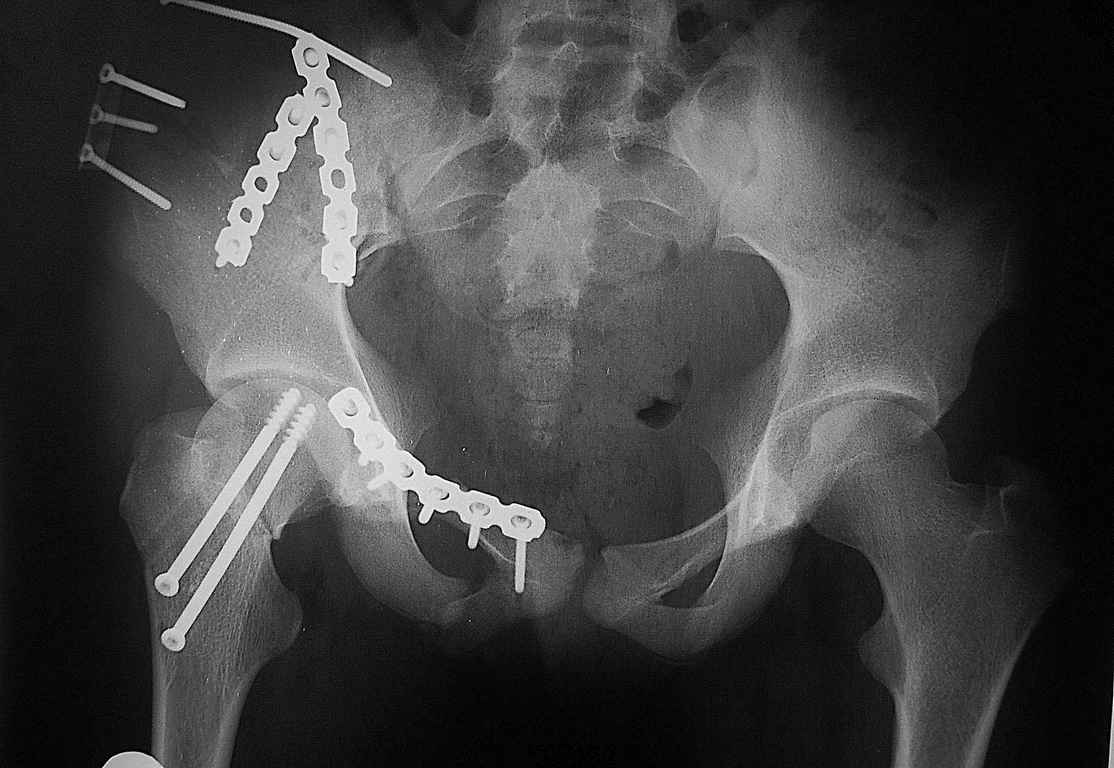

Шейку срочно закрыто винтами.

Таз - подвздошным и падлобковым доступом раздельные рекострукционные пластины 4 штуки. Сплошную пластину как у взрослых нельзя (из-за роста придется доставать)

1 аппаратом сложно управлять при оскольчатом переломе крыла

2 для будущей мамы желателен максимально восстановленный таз

3 нет нужды в спецуходе,

4 легче ходить 6 мес (из-за шейки) на одной ноге

Операция была на прошлой неделе, коллеги обещали выставить результат и комментарии.

Уважаемые коллеги огромное спасибо за советы! Больная была прооперирована А.В.Рунковым.